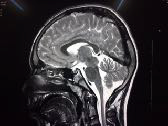

MRI shows Cervical cord atrophy

Results: In our study, there were 25 patients with clinical phenotype satisfying Harding’s criteria for Friedreich ataxia. The number of males were 15(60%) and females were 10(40%). The mean age at onset of symptoms was 11 years. Twenty four(96%) patients had gait ataxia at initial presentation. Twenty one patients had reported speech disturbances(84%). Vision impairment and hearing impairment was reported in one patient. Twenty two(88%) patients had cerebellar dysarthria and 4(16%) had square wave jerks. Cardiac abnormality was found in 5 patients. MRI brain showed cervical cord atrophy in 23(92%) and cerebellar atrophy without cord atrophy in 2(8%). FRDA gene was positive in 21(84%) and 4(16%)were negative. The mean IQ score was 52.33 ± 7.45.

Conclusion: Friedreich Ataxia is a rare autosomal recessive cerebellar ataxia with neurological and non neurological manifestations involving the Frataxin gene. MRI predominantly shows cervical cord atrophy and many patients have low IQ.